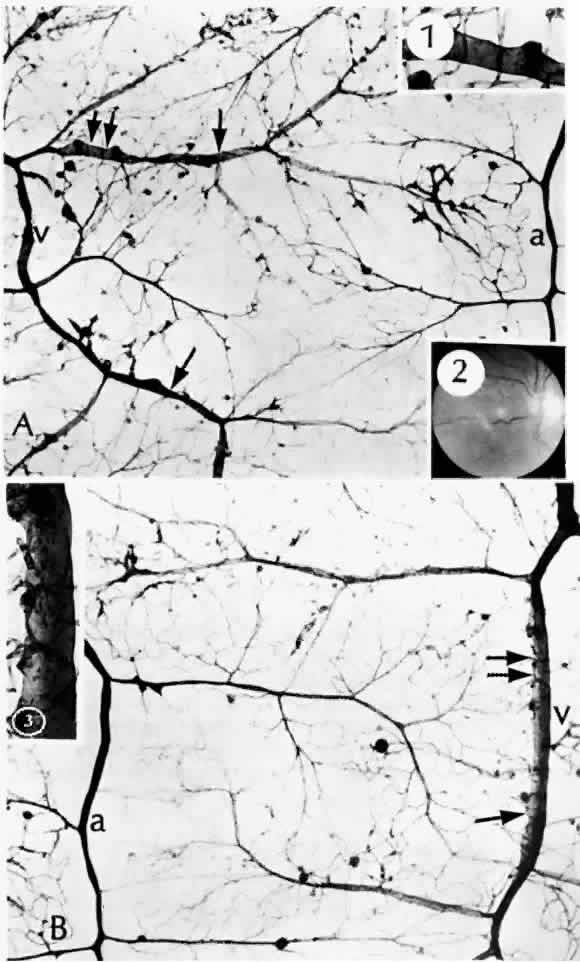

As shown by trypsin digestion, capillary pericytes are lost first,27 followed by endothelial cells (Figs. 6 and 7). Aldose reductase, one of the enzymes in the sorbitol metabolic pathway, is present in significant quantities in retinal capillary pericytes, but not in endothelial cells, and may thus be implicated in the formation of microaneurysms.37 The final result is an acellular segment of capillary that is nonperfused on fluorescein angiography.36

Fig. 6. Diabetic retinal capillary. A. Basement membrane shell (arrows) is the only remaining indication of where the pericytes had been. B. Nondiabetic normal capillary shows the basement membrane shell (arrow) around the pericyte. C. Diabetic capillary has only a basement membrane shell (arrow), with the nucleus absent. (A, PAS, × 630; B, PAS, × 850; C, PAS, × 630)

Fig. 7. Retinal capillary microaneurysm (RCM). A. RCMs occur in random distribution between the arteriole (a) and venule (v). “Young” RCMs are seen as saccular capillary outpouchings with proliferated endothelial cells (arrows). “Old” RCMs appear as solid black balls with their lumens obliterated by PAS-positive material. Note the darker color of the capillaries with thickened basement membranes and arteriolar-venular connections. B. Very large RCM (arrow) or the tiny hemorrhages associated with abnormal vessels are probably responsible for the RCMs seen clinically. (A, PAS, × 40; B, PAS, × 115)